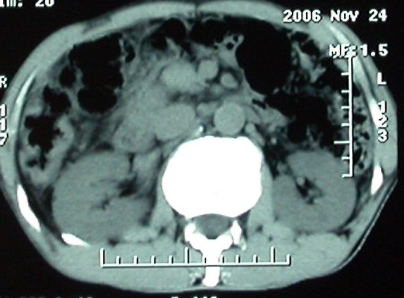

标题: 上腹隐痛、饱胀、消瘦2-月。

增强ct所见【动脉增强期】